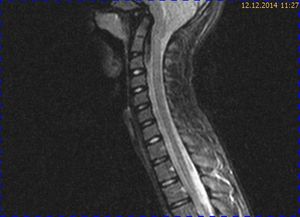

Abb. 2.1 Sagittales MRT (T2 TSE, 1,5 T): bei unveränderter Streckfehlhaltung der HWS 2 Monate nach der Erstuntersuchung Progredienz des Tonsillentiefstands, Syringomyelie

Abb. 3.1 T2 TSE sagittal: progrediente intraspinale Tonsillendislokation mit nachweisbarem Ödem des Zervikalmarks in Höhe von HWK 2

Abb. 3.2 T2 TIRM: das intramedulläre Ödem wird durch die Tonsillenkompression reproduzierbar dargestellt, betonter Zentralkanal des Halsmarks

Bei dieser Untersuchung wurde übersehen, dass die Kleinhirntonsillen in das Foramen magnum disloziert waren und eine Arnold-Chiari-Malformation mit Erweiterung des 4. Ventrikels und des Aquäduktes inklusive Kleinhirntonsillentiefstand vorlag. Bei zwischenzeitlich auswärtig erfolgtem CT der HWS wurde eine Anlagestörung im kraniozervikalen Übergang beschrieben. Eine Kontrolluntersuchung des Kopfes weitere 4 Monate später dokumentierte neben einem medullären Ödem einen progredienten Tonsillentiefstand, der zur neurochirurgischen Behandlung mit operativer Erweiterung des Foramen magnum führte.